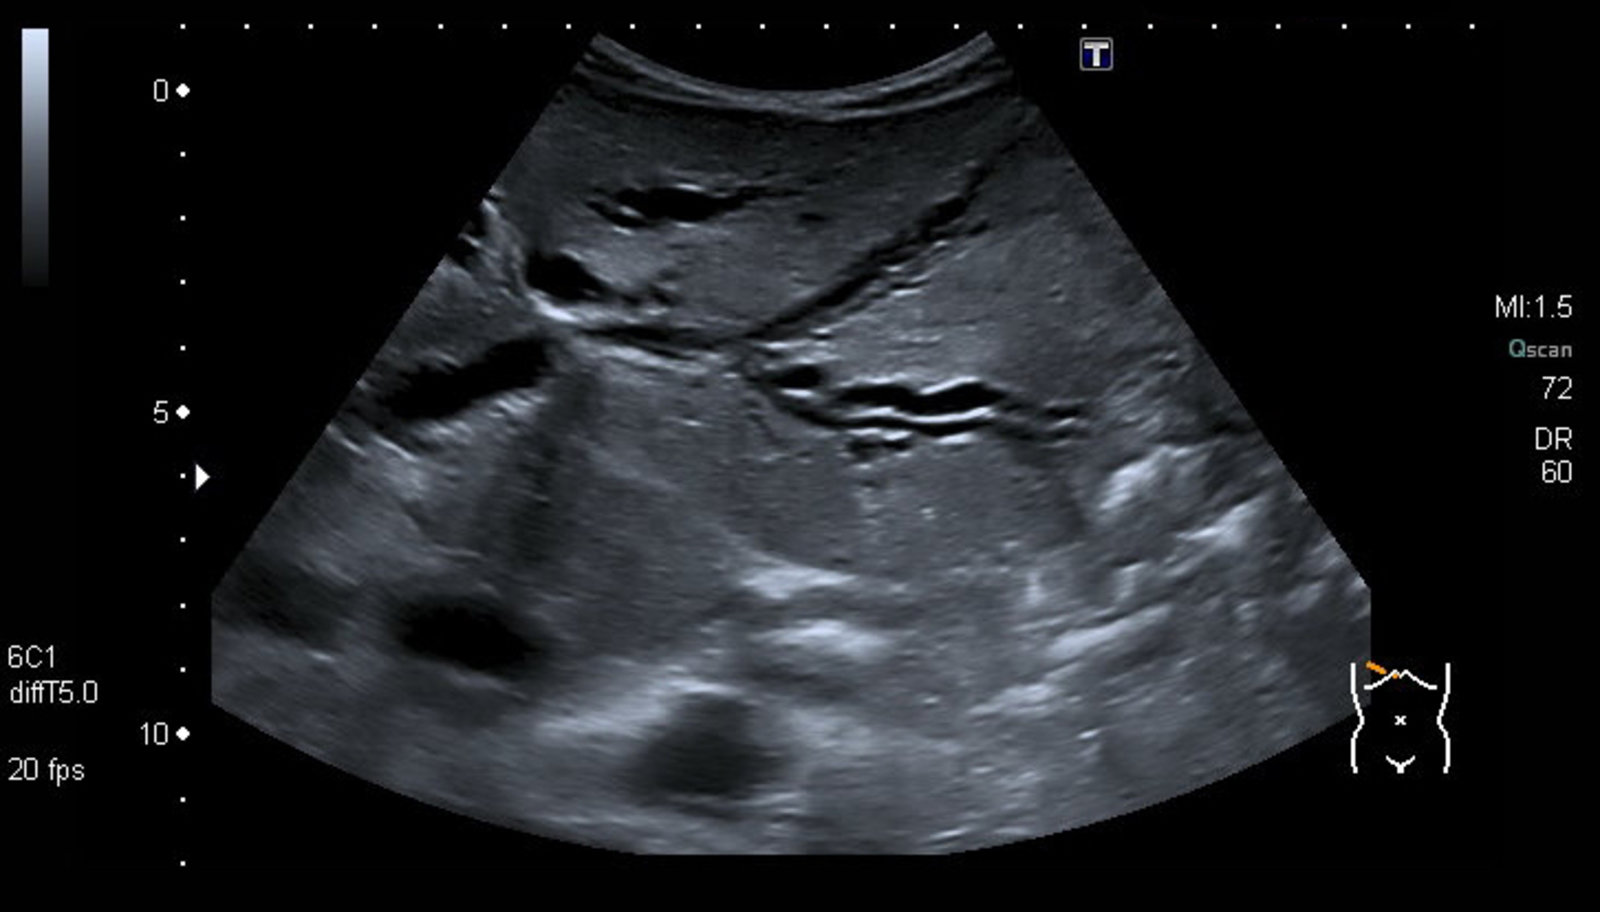

RUQultrasound

• Indication: : preferred first-line imaging modality in patients presenting with suspected cholangitis [8][11][12]

• Supportive findings

• Dilated common bile duct: See ''Diagnosis of choledocholithiasis” for details.

• Dilated intrahepatic bile ducts: indicates obstructive cholestasis

• Thickened bile duct walls [13]

• Evidence of underlying etiology, such as:

• Choledocholithiasis: occluding CBD stone with/without cholelithiasis may be visualized [14]

• Biliary stricture: focal narrowing of the bile duct(s), with dilation of the proximal biliary tree

• Biliary tumor: intraluminal mass within the bile duct

RUQultrasound is not sufficiently sensitive to definitively rule out biliary obstruction. Obtain cross-sectional imaging (i.e., CT abdomen or MRCP) in patients with a high pretest probability of acute cholangitis and a negative RUQultrasound. [8]